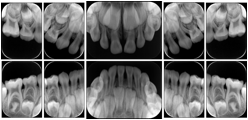

2. A patient requests cosmetic surgery to enhance their facial appearance. The case requires consultation between an orthodontist in New York and an oral surgeon in California. The cephalometric series of 2D projections constructed from a volumetric CT data set that is used for the discussion is arranged by a Structured Display for transfer between the two practitioners.

Cephalometric Series Structured Display

Figure OO-2. Cephalometric Series Structured Display